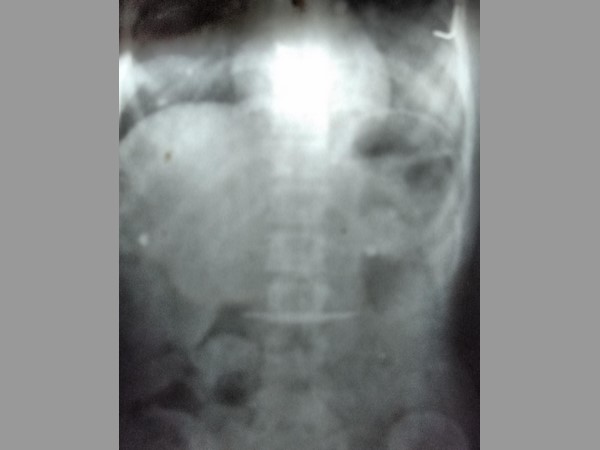

ఈ విషయాన్ని ఇంట్లో వారికి చెప్పకుండా చాలా రోజులు దాచిపెట్టింది. అయితే కొన్నాళ్లకు కడుపునొప్పితో అనారోగ్యానికి గురైంది. దీంతో స్ధానిక వైద్యులను సంప్రదించగా ఎక్సరేలో పదునైన ఆరంగుళాల కత్తి గొంతులో నుంచి కడుపులోకి చేరినట్టు డాక్టర్లు నిర్ధారణకు వచ్చారు.

అయితే కొన్నాళ్లకు కడుపునొప్పితో అనారోగ్యానికి గురైంది. దీంతో స్ధానిక వైద్యులను సంప్రదించగా ఎక్సరేలో పదునైన ఆరంగుళాల కత్తి గొంతులో నుంచి కడుపులోకి చేరినట్టు డాక్టర్లు నిర్ధారణకు వచ్చారు. దీంతో వెంటనే ఆమెను హైదరాబాద్లోని గాంధీ ఆసుపత్రికి తరలించారు.